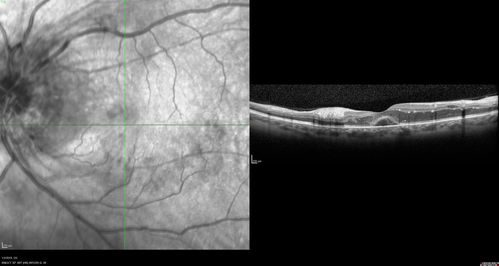

Grade 4 hypertensive retinopathy

55 year old man Hhe did have headaches a few weeks ago and also some nausea and vomiting.  He noticed for a few weeks the vision in the left eye was blurred and  that the vision in the left eye is dark.

VA OD: Dcc20/20

VA OS: Dcc20/100-1

He was admitted directly to ICU for blood pressure control (290 / 170 mmHg)

3 weeks later his VA increased to 20/20 OD, 20/32 OS